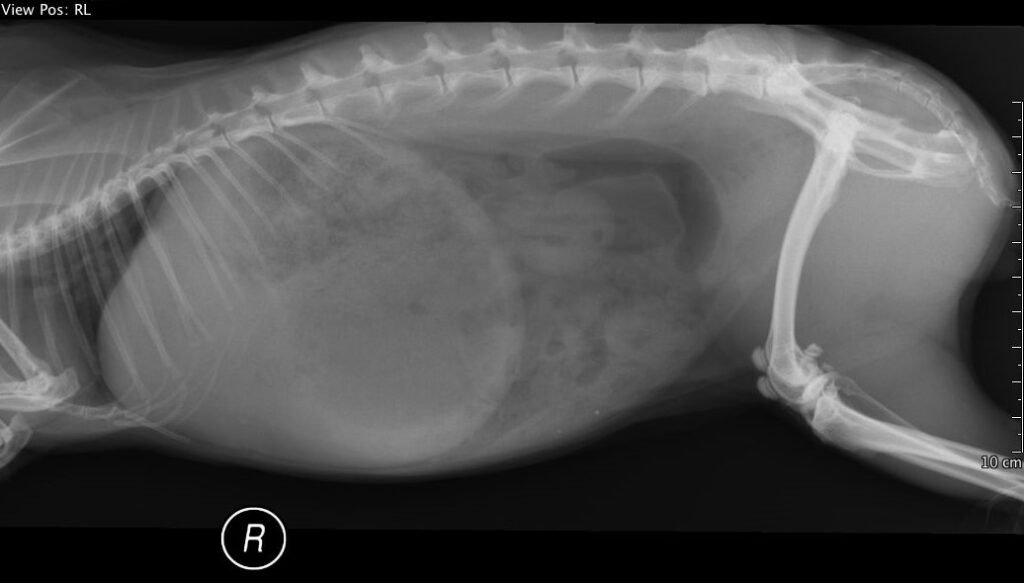

(عانى هذا الأرنب من انتفاخ معوي حاد. كانت العلامة السريرية الرئيسية هي فقدان الشهية. من المهم عدم إطعام هذه الأرانب قسرًا. يُعالج هذا المرض بإعطاء المريض سوائل وتسكين الألم بشكل مكثف.)

العلاج

- الاستقرار العام أولًا

- سوائل وريدية بجرعة مضاعفة تقريبًا عن الاحتياج اليومي (10 مل/كغ/ساعة).

- تسكين ألم فعّال (مثل الأفيونات المناسبة للأرانب).

- مراقبة الحرارة والجفاف.